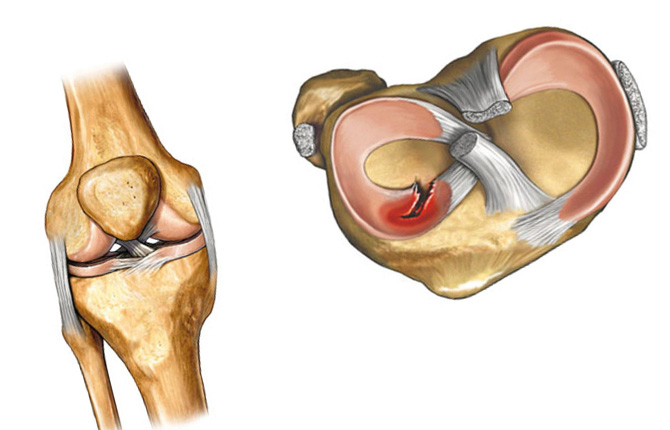

Анатомические изображения менисков и коленного сустава